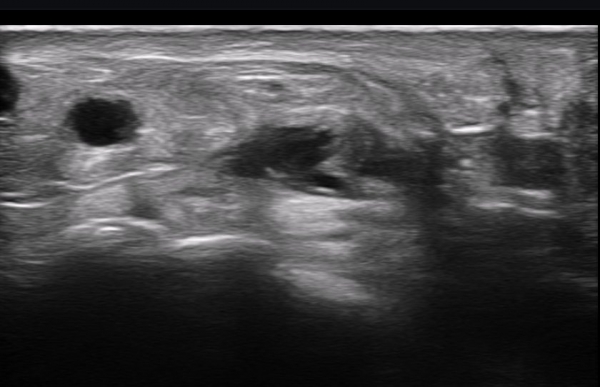

ÃÊÀ½ÆÄ ¼Ò°ß : ºñº¹½Å°æ Ⱦ´Ü¸é°Ë»ç¿¡¼­(»çÁø 1~13) ºñº¹½Å°æÀÇ Àú¿¡ÄÚ ºÎÁ¾°ú ´Üºñ°ñ°Ç³» ³¶Á¾¼º º´º¯ÀÌ °üÂûµÈ´Ù.